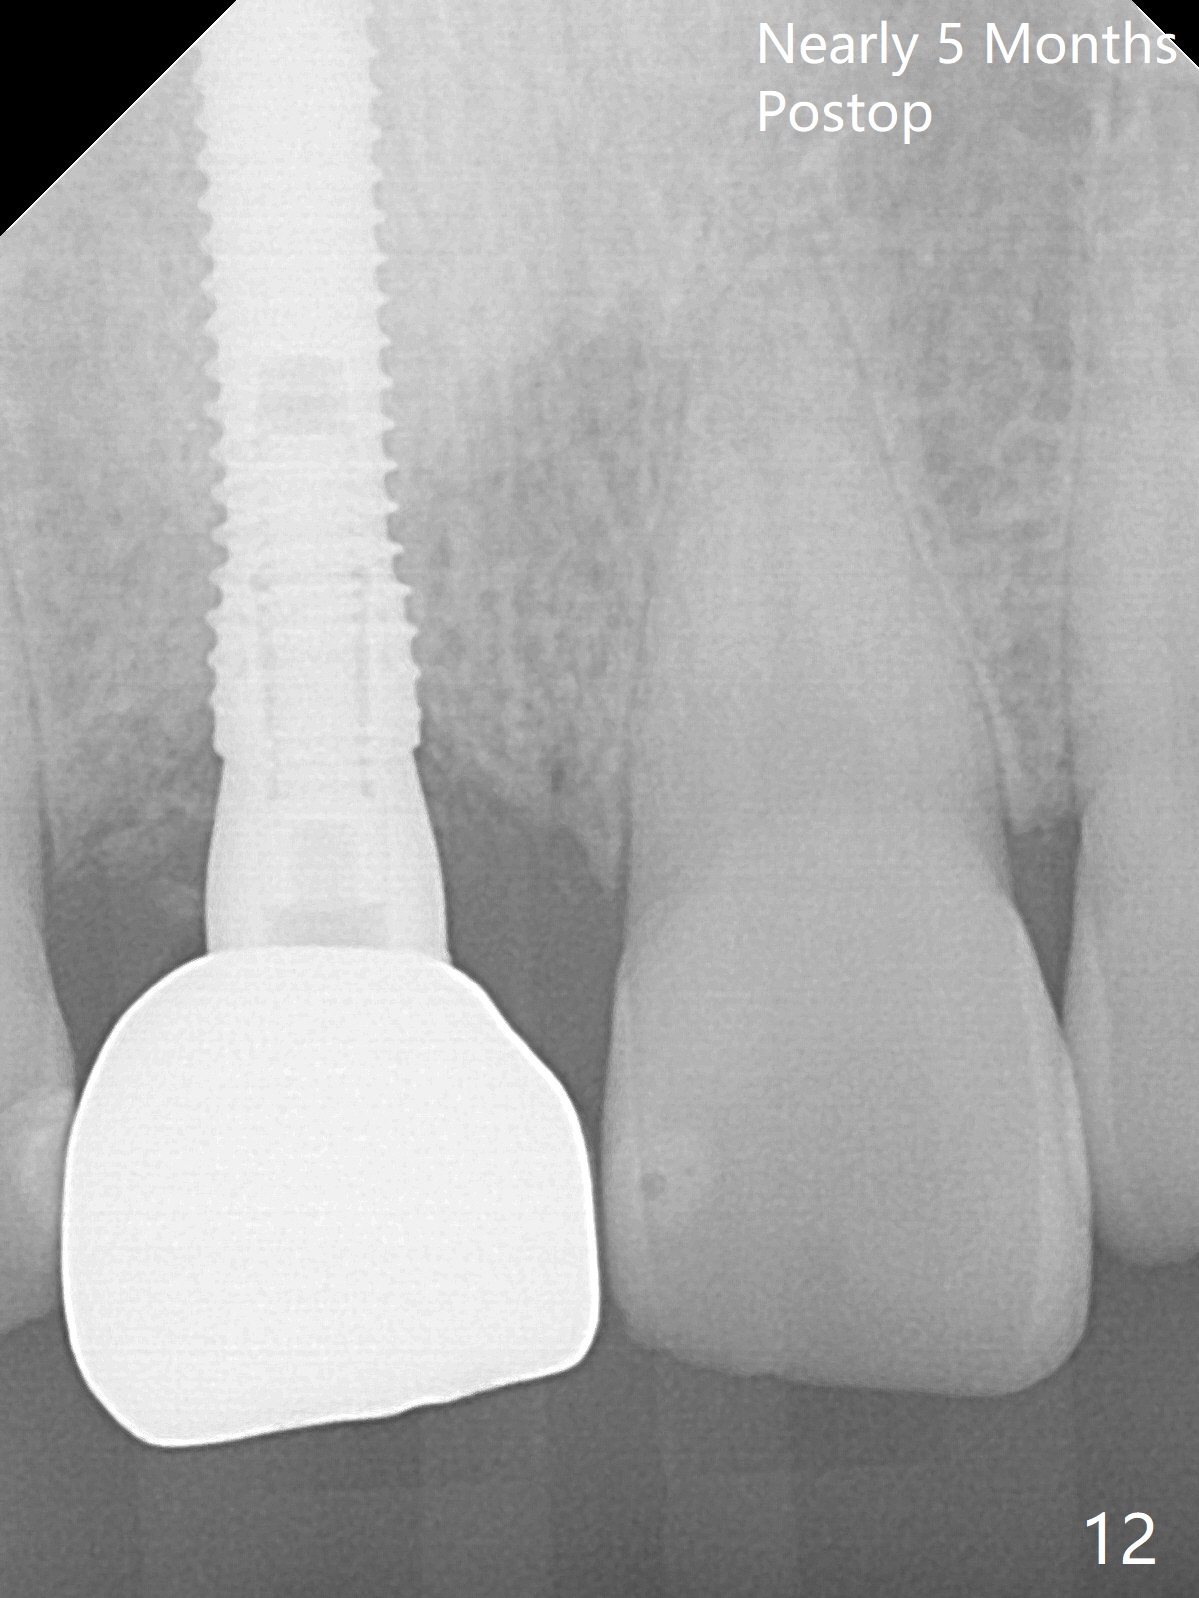

The buccal gingiva at #8 is erythematous (Fig.1: *), which is associated with the tooth fracture line (Fig.2 with granulation tissue: *). The buccal plate remains intact. Osteotomy is initiated in the palatal wall of the socket (Fig.3,4). The initial osteotomy depth is 16 mm (Fig.5); the trajectory is going to be adjusted as shown by arrows. The trajectory improves when a 3.8x15 mm dummy implant is placed (Fig.6). The definitive implant (3.8x16 mm) appears to be placed at an appropriate level (Fig.7). A 4.5x3 mm temporary abutment is inserted for an immediate provisional. As routine, Vera Graft is placed in the buccal gap. The buccal gingival erythema reduces without tenderness 1 week postop (Fig.8). Although the provisional is unstable, there is no bone loss 2 months 20 days postop (Fig.9). Because of the loose provisional (partial detachment from the underlying temporary abutment), impression is taken earlier (3 months postop, Fig.10,11). Due to the pointed abutment tip, the crown is redone 3 times. By the time of cementation (nearly 5 months postop), the socket appears to have healed (Fig.12).